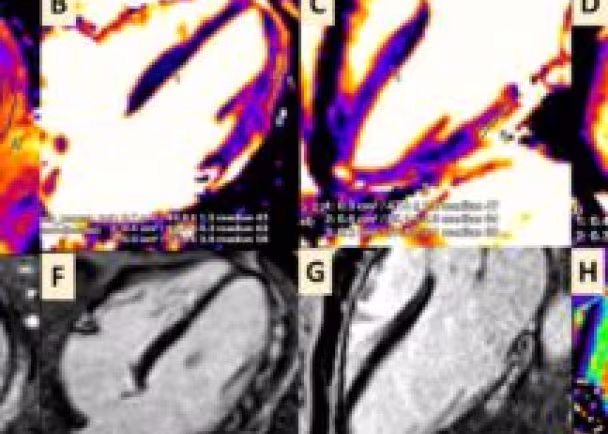

The research reports CMR imaging findings in four cases of acute myocarditis using a unique institutional imaging protocol implemented at Abbott Northwestern Hospital by João Cavalcante, MD, MHIF researcher, director of the CMR lab and co-author of the manuscript. The imaging protocol uses a combination of parametric T1, T2 and extracellular (ECV) mapping along with traditional late-gadolinium imaging to identify myocardial edema and non-ischemic injury, both of which support acute myocarditis as per updated Lake Louise criteria (LLC). LLC provides established diagnostic imaging criteria and uses tissue-based CMR markers to identify the presence of myocarditis.

Cardiac magnetic resonance (CMR) imaging showing acute myocarditis temporally related to the receipt of mRNA COVID-19 vaccination in four cases (16-31 years) raises the interesting possibility about a potential immune-boosting mechanism after prior immune exposure or priming (Figure).